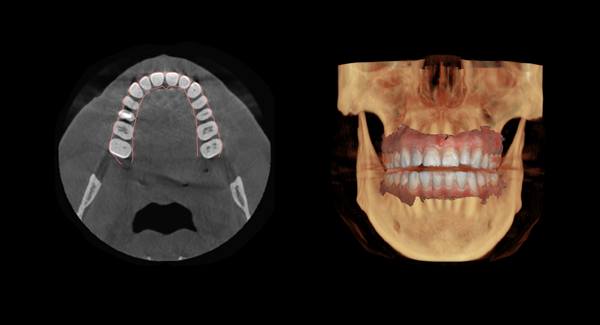

Sponsored article: How Automatic Dose Control is advancing patient safety in CBCT for emergency surgeries

Probo Medical sets out the importance of Cone Beam CT, an innovative technique used in modern dental and maxillofacial imaging